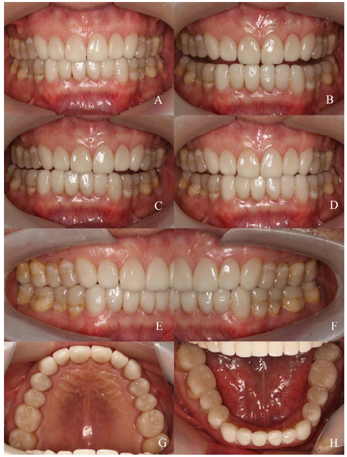

垫 D 戴入口内,此时咬合垂直距离较原临时修复体升高 E 通过下颌运动磨除多余雕刻蜡获取咬合面形态,回到原来的垂直距离 F 获得的功能性咬合面形态4.精细牙体预备、取模,制作前牙唇贴面、后牙

贴面,完成正式修复

患者对修复效果满意,1年后复查,修复体及基牙稳定,患者无不适症状。

本病例中,患者全牙列重度磨耗,垂直距离丧失,但牙体组织的缺损主要位于咬合面,且患者无明显疼痛不适症状,牙周情况良好,牙髓活力正常,X线片未及明显根尖周病变及牙槽骨吸收。这种情况若使用全冠进行修复需要去除约70%的牙体硬组织,既增大了出现牙髓并发症的风险,又使基牙抗力减小,不利于修复体的长期稳定[2]。对于此类因磨耗导致咬合面硬组织缺损、牙髓活力正常,需要重建咬合面形态的患牙,使用

贴面修复有着较好的临床效果。Edelhoff等[5]对103颗二硅酸锂玻璃陶瓷贴面进行5.9~11.6年(平均7.9年)的前瞻性研究,结果显示其存留率达100%,Arnetzl等[6]临床随访286例长石类可切削瓷贴面,93个月后存活率可达99.3%。本病例使用

贴面重建咬合后,患者对治疗效果满意,1年后复查基牙及修复体无异常、咬合及垂直距离保持稳定,显示了良好的修复效果和稳定性。